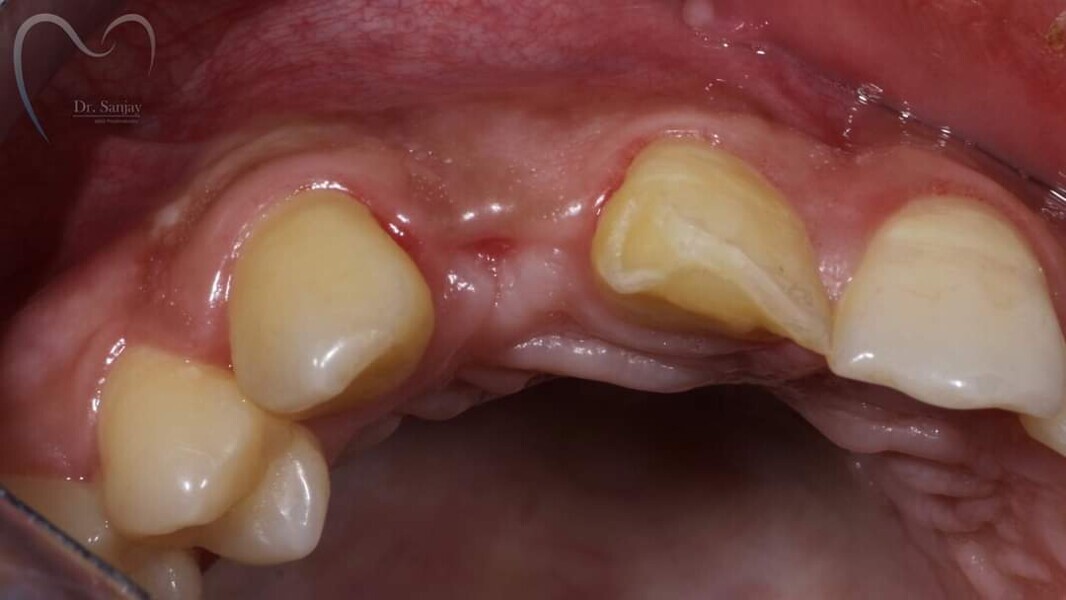

Esthetic Rehabilitation of Maxillary Anterior Teeth: Dr Sanjay Sah